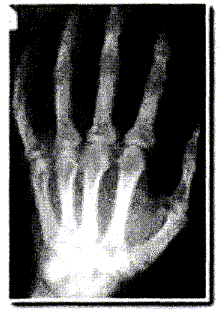

La radiographie enregistre l'image d'un corps traversé par un faisceau de rayons X. Suivant la constitution du corps, les rayons X sont plus ou moins absorbés et le film photographique, placé derrière le corps radiographié, est ainsi plus ou moins impressionné. Le document ci-dessous correspond à la radiographie d'une main. La main placée contre la plaque sensible s'intercale entre la source de rayons X et la plaque.

Les éléments calcium ( Z=20) et phosphore ( Z= 15) sont particulièrement présents dans les os.

Les éléments carbone (Z=6), hydrogène ( Z=1) et oxygène ( Z=16) sont les principaux éléments constitutifs des tissus.

Lorsque l'absorption est importante, ( une grande partie des rayonx X est arrêté ), peu de rayons atteignent le film : le film est peu impressionné. ( teinte blanche)

Lorsqu'il n'y a aucune absorption ( en dehors de la main par exemple ) , tous les rayons X atteignent le film et l'impressionnent ( teinte noire).

Lorsque l'absorption est faible, ( une petite partie des rayonx X est arrêté ), beaucoup de rayons atteignent le film : le film est assez impressionné. ( teinte grise)

Les os absorbent fortemment les rayons X et apparaissent en blanc.

Les tissus absorbent peu les rayons X et apparaissent en gris.

L'absorption des rayons X est d'autant plus importante que le n° atomique de l'élément chimique est grand.